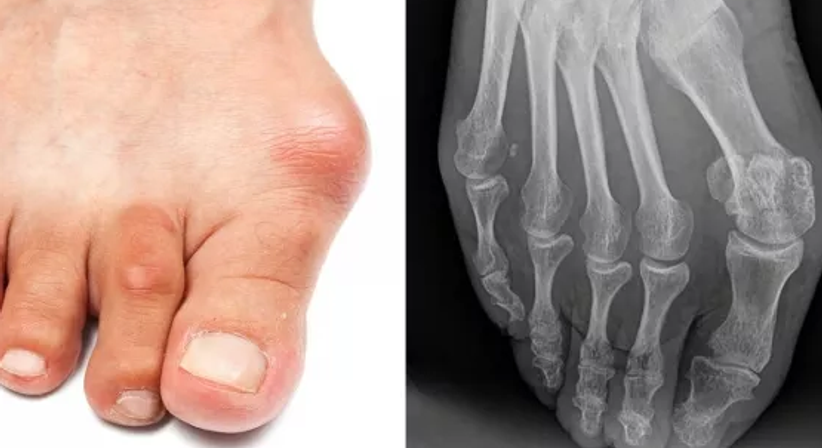

Beim Hallux valgus, auch als Überbein, Frostballen, Ballenzeh oder Schiefzehe bezeichnet, handelt es sich um die häufigste Fehlstellung des Vorfußes, bei der sich das Grundgelenk der Großzehe nach außen neigt. Durch die Abspreizung des ersten Mittelfußknochens kommt es zu einer Breiterstellung des Vorfußes und einer sichtbaren Wölbung am Großzehengrundgelenk.

Aufgrund der vermehrten Druckbelastung am Großzehengrundgelenk kann es zu schmerzhaften Entzündungen (Bursitis) und Bewegungseinschränkungen (Schmerzen beim Gehen oder längerem Stehen) sowie Rötungen und Schwellungen über dem Großzehengrundgelenk kommen. Bei manchen Patienten entwickeln sich aufgrund des Spreizfußes und der Veränderung in der muskulären Balance am Vorfuß auch sogenannte Hammer- oder Krallenzehen.

Für die Entstehung eines Hallux valgus gibt es mehrere Ursachen. Neben dem Tragen von zu spitzen, engen und hohen Schuhen kann z.B. eine genetisch bedingte Bänder- und Bindegewebsschwäche zu einem Hallux valgus führen.

Zu Beginn kann ein Hallux valgus konservativ mittels Einlagen, Schmerztherapie oder physikalischen Maßnahmen behandelt werden. Bei einer fortgeschrittenen Fehlstellung wird in der Regel eine operative Korrektur durchgeführt.

Nach klinischer und radiologischer Untersuchung sowie Vermessung der vorliegenden anatomischen Gegebenheiten kommen, je nach Grad der Großzehenabweichung, spezielle operative Verfahren (u.a. OP nach Austin bzw. Chevron-Osteotomie) zur Gradstellung des ersten Strahls zum Einsatz. Dazu reicht ein kleiner Schnitt über dem Großzehengrundgelenk. In manchen Fällen ist es notwendig, die durchgeführte Osteotomie mit speziellen Schrauben oder Platten zu fixieren.